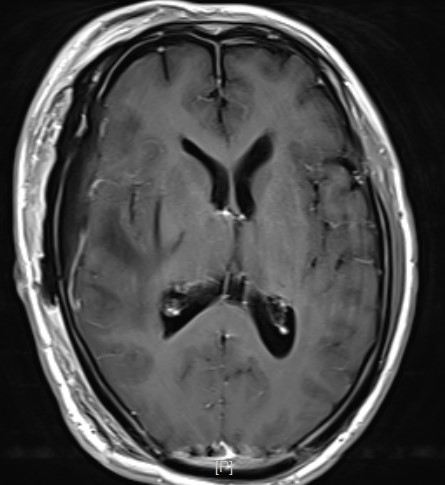

右侧扩大翼点开颅,显微镜下切除肿瘤

术后复查肿瘤近全切除

术后病理:弥漫性胶质瘤高级别

患者术后恢复良好,肢体活动可,能自主下床活动